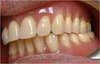

Contrôle: prothèse transvissée en bouche

Avant/Après